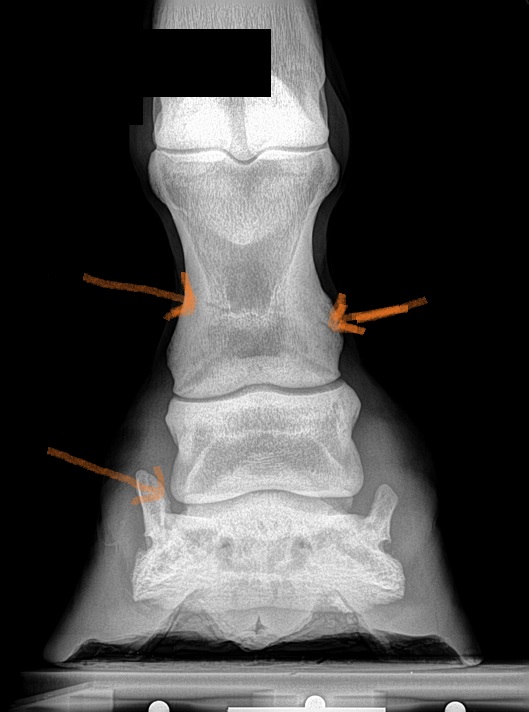

Location: Finally horseback again.... | Let me see if this works. I am by no means a radiologist but Ive looked at a lot of x rays. The areas I pointed to, raise questions. The joint appears to have some calcification that makes the appear not smooth. The other areas are what I believe may be the areas of concern the previous poster saw.

(x ray 3.jpg)

I am not an X-ray guru but is there a pastern fracture, I see abnormalities on both X-rays in the same spot. |

Location: North Dakota | sophiebelle - 2014-07-08 2:51 PM cheryl makofka - 2014-07-07 7:17 PM I am not an X-ray guru but is there a pastern fracture, I see abnormalities on both X-rays in the same spot. Cheryl, I certainly am not tech savvy enough to do what I'm asking you to do, but I am very interested in where you see a fracture. I think I see it on the second, but nada on the first. You've peaked my interest, so would/can you draw a line or a circle in the area that you see? To the OP, you came on asking on how to improve your runs. I think the advice you are getting is in earnest and helpful. While you may not like the thread changing to a lameness thread, if that is what they see (I can't get your video to load) then it gives you somewhere to start. Correct me if I'm wrong Cheryl, but pastern bone, right hand side, looks like a hairline fracture!!! Bones and joints should have a "I look the same" on both sides.

| Canchasr1 - 2014-07-08 4:16 PM

Let me see if this works. I am by no means a radiologist but Ive looked at a lot of x rays. The areas I pointed to, raise questions. The joint appears to have some calcification that makes the appear not smooth. The other areas are what I believe may be the areas of concern the previous poster saw.

The seen the ones on the pastern but not on the coffin joint, thanks for placing the arrows, I haven't even figured out how to upload pictures or videos lol |

I am assuming you put wedges on for coffin bone dropping? In the rads did you see any changes in the pastern joint - osteophytes, enthesiophytes? That may be the front end issue, but it gets missed sometimes because we get carried away looking at P3. You mentioned that "nothing has changed since last year" can't tell if you are referring to the joint space or not. Even if nothing has changed since last year, if he is still sore, and there is calcification, that may be the issue.

And as far as the x-rays go, there have been a second set of eyes who have looked at them. It may not be a fracture. It might just be a disturbance in the growth plate. I'll need to get x-rays of his right leg because if that is the case, it will be the same in both legs.

The issue does not appear to be navicular.

Someone pointed an arrow at one of the joint spaces and that appears to be a lateral cartilage bone spur that will eventually turn into a side bone. |